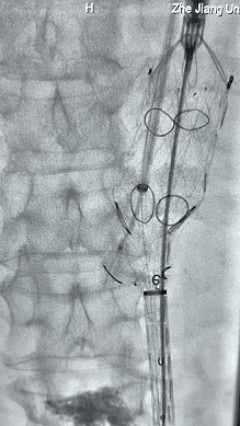

7. 经长鞘重新选入左侧外分支,并超选进左肾动脉,沿导丝送入外周血管覆膜支架7*60mm一枚,并予以球囊后扩张,手推造影显影良好。

17.gif

8. 从右侧股动脉入路送入腹主支架AB-24-12-110-S,近端重叠胸腹主动脉支架远端,调整好支架位置后释放。

9. 经左股动脉送入导丝导管,超选进腹主动脉支架短腿内,后沿导丝送入髂支,同理,右侧沿导丝送入髂支并释放,使用先健顺应性球囊后扩各支架连接处及支架近远端,最后通过预留导管向瘤腔注入人纤维蛋白粘合剂数支,造影显示分支通畅。

19.gif